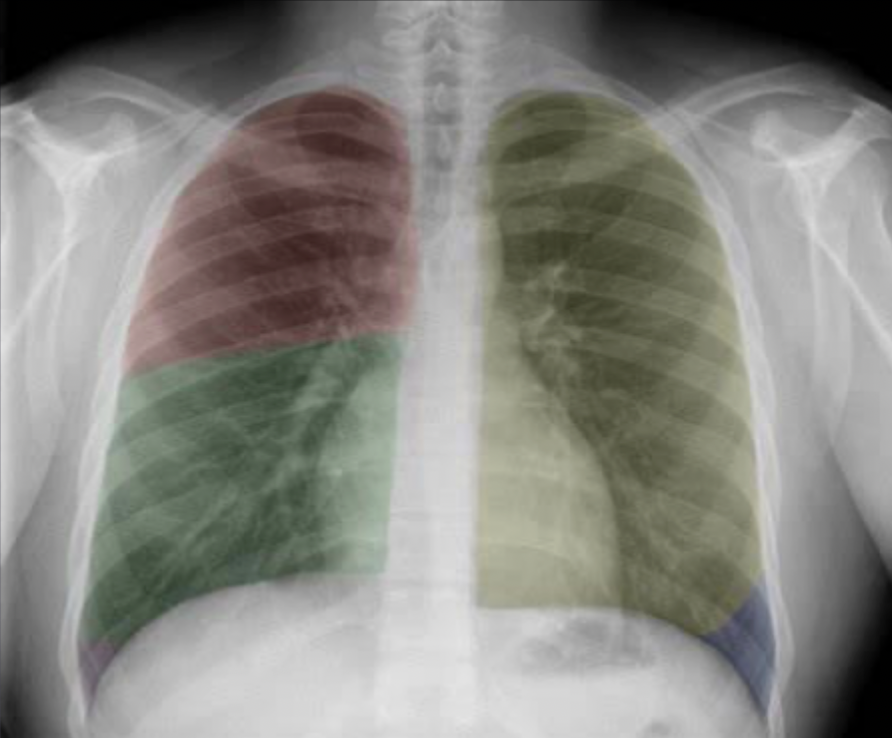

Which lobe is which ?

Red: right upper lobe (RUL)

Green: right middle lobe (RML)

Purple: right lower lobe (RLL)

Yellow: left upper lobe (LUL)

Blue: left lower lobe (LLL)